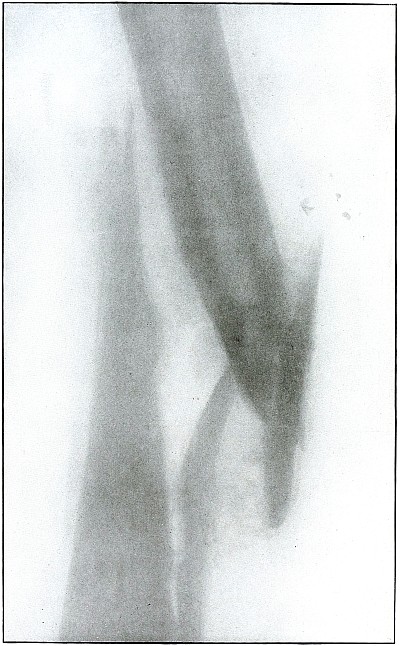

| 59. |

Gunshot wound, knee |

128 |